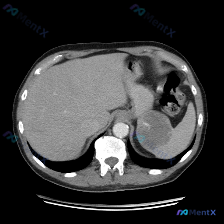

这是一份腹部CT横断面(软组织窗,单帧图像)的客观描述:

- 肝脏:形态、密度大致正常,未见明确占位。

- 脾脏:这是核心异常——可见一较大类圆形低密度占位,边界相对清晰,但内部密度不均匀,可见部分稍高密度区域,病灶占据了脾脏较大范围。

- 胰腺、双肾、大血管:胰腺体尾部及脾周受挤压显示欠清,但未见明确胰实质肿块;双肾及腹主动脉、下腔静脉走行尚可;腹腔未见大量积液。